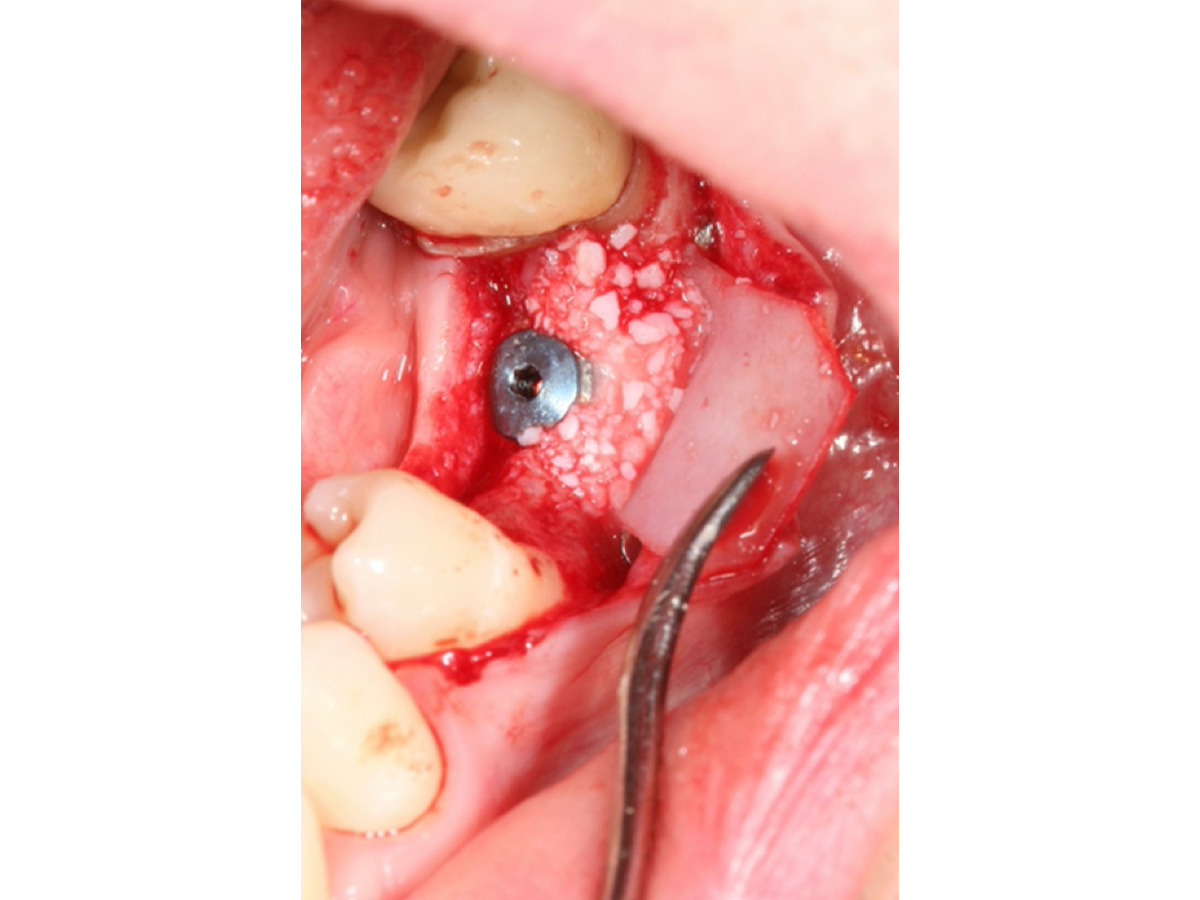

Nach Implantation wurde die zugeschnittene Bone Lamina positioniert und mit Pins fixiert, die Situation danach ist in Abb. 5 zu sehen. Mit dem Instrument wird demonstriert, dass eine „Tasche“ geschaffen wurde, die in Abb. 6 mit mp3® Knochengranulat aufgefüllt wird. Abb. 7 stellt dar, wie die Bone Lamina über den Kopf des Implantates auf den lingualen Anteil des Kieferkammes positioniert wird.

Nach Implantation: Positionierung und Fixierung der Bone Lamina.

Abbildung 5